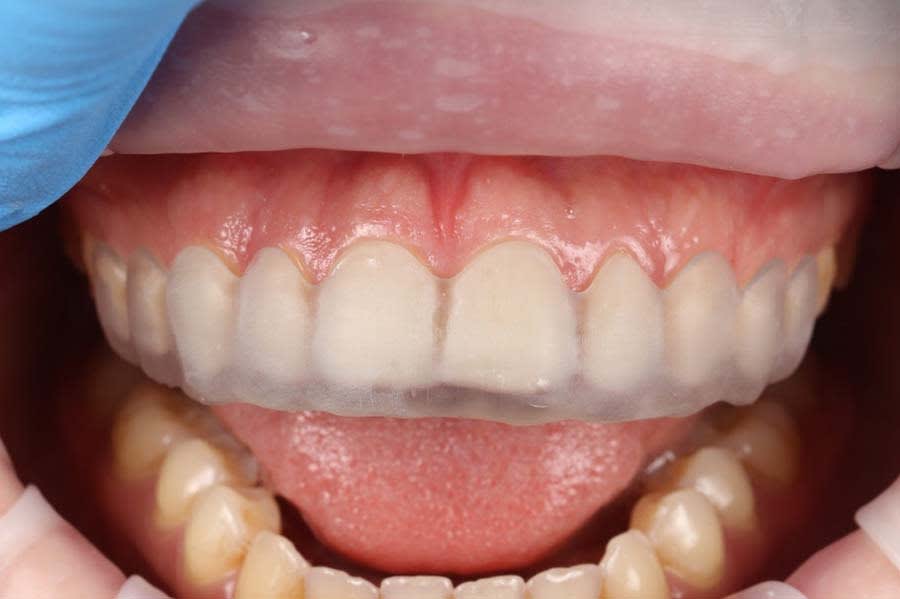

All prepared surfaces were refined with fine-grit diamond burs to smooth micro-irregularities, reduce chipping risks, and improve adaptation.9 Final polishing was done with soft brushes and polishing pastes to remove residual roughness and prepare for provisional restorations (Figure 7). Temporary restorations, fabricated from matrices based on the wax-up, were placed to protect prepared tissues, stabilize the gingival contour, and allow the patient to adapt to esthetic and functional changes.

During the provisional phase, clinical adjustments were made, including refining smile line parameters, lip support thickness, phonetic features, and harmony with facial soft tissues. The provisional restorations enabled critical feedback on esthetics and function (Figure 8).10 These adjustments were documented and incorporated into the final CAD design. Final documentation included photographs of prepared teeth (Figure 7), provisional restorations (Figure 9), and gingival contours to communicate with the laboratory and facilitate treatment accuracy.